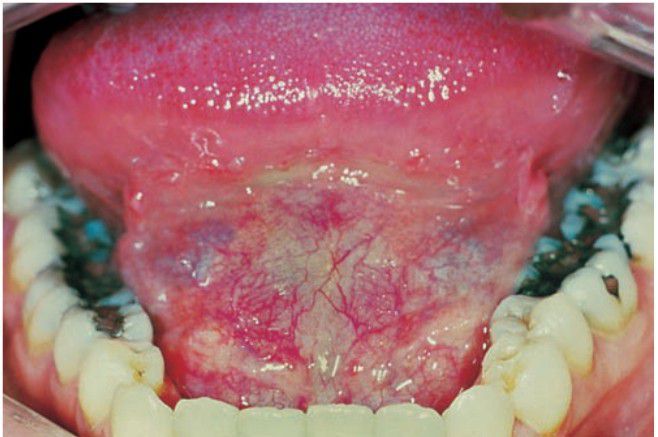

Dermoid cyst

Intraorally dermoid cyst presenting itself as a midline swelling in the floor of the mouth

Sublingual dermoid cyst